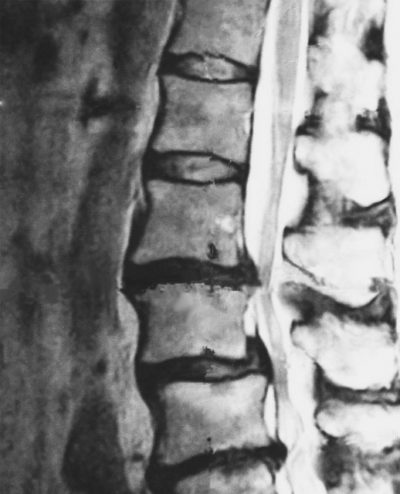

椎間板ヘルニア?で浦安の整骨院・整体院をお探しでしたら

こんにちは!千葉県浦安市のくりた整骨院 院長の栗田です。 ここ数日は春らしいお天気が続き 暖かいですね! その分,『花粉』の飛散量も多く, 花粉症の方には辛い日々ですが。。。(>_<) さて,さ […] -

浦安市で腰痛でお困りの方,それってホントに椎間板ヘルニア・脊柱管狭窄症が原因?

こんにちは。東西線浦安駅より徒歩4分 浦安魚市場目の前にある『くりた整骨院』院長の栗田です。 朝晩の冷え込みが一段と増してきましたね。 皆さん体調はいかがですか?寒くなってくるとご相談が多くなってくるのが 『腰痛』でお悩 […]